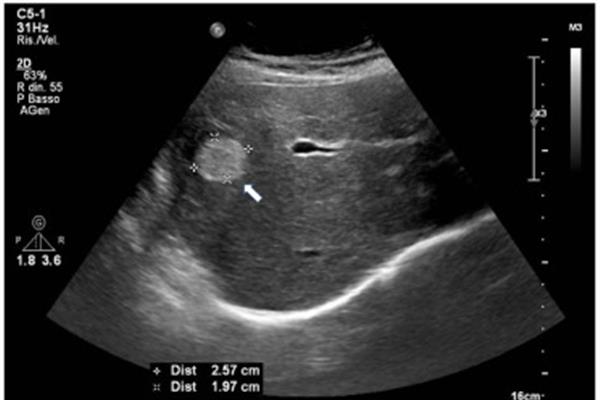

پولیپهای کیسه صفرا زائدههایی هستند که از دیواره داخلی کیسه صفرا بیرون میآ ...

اگر اخیراً متوجه وجود پولیپ کیسه صفرا در بدن خود شدهاید، شاید این سؤال برایتان پیش آمده باشد که آیا این پولیپ خطرناک است؟ در این مقاله، درباره پولیپهای کیسه صفرا، روشهای شناسایی از طریق سونوگرافی، علائم، خطرات و گزینههای درمانی صحبت میکنیم.

پولیپهای کیسه صفرا زائدههایی هستند که از دیواره داخلی کیسه صفرا بیرون میآیند. در بسیاری از موارد، این پولیپها خوشخیم و بیخطر هستند، به این معنا که سرطانی نیستند. حدود ۹۵٪ از پولیپهای کیسه صفرا غیرسرطانی هستند و معمولاً در حین سونوگرافیهای روتین شکم یا بررسیهایی که برای سایر دلایل انجام میشوند، کشف میشوند.

بیشتر پولیپهای کیسه صفرا بهندرت سرطانی میشوند، اما اندازه پولیپ میتواند در تعیین خوشخیم یا بدخیم بودن آن مؤثر باشد. بهطور کلی، سونوگرافی پولیپ یکی از راههای اولیه برای تشخیص اندازه و خطرات احتمالی پولیپها است:

پولیپهای کوچک (کمتر از ۱۰ میلیمتر): پولیپهایی که اندازهشان کمتر از ۱۰ میلیمتر باشد، به احتمال زیاد سرطانی نیستند و معمولاً نیازی به درمان ندارند. با این حال، توصیه میشود سونوگرافیهای دورهای برای بررسی تغییرات احتمالی انجام شود.

پولیپهای بزرگتر از ۱۰ میلیمتر: پولیپهایی با اندازه بیش از ۱۰ میلیمتر میتوانند خطر سرطانی شدن داشته باشند. برای این نوع پولیپها، سونوگرافی منظم پولیپ و در صورت نیاز کولهسیستکتومی (برداشتن کیسه صفرا) توصیه میشود تا از خطرات جلوگیری شود.